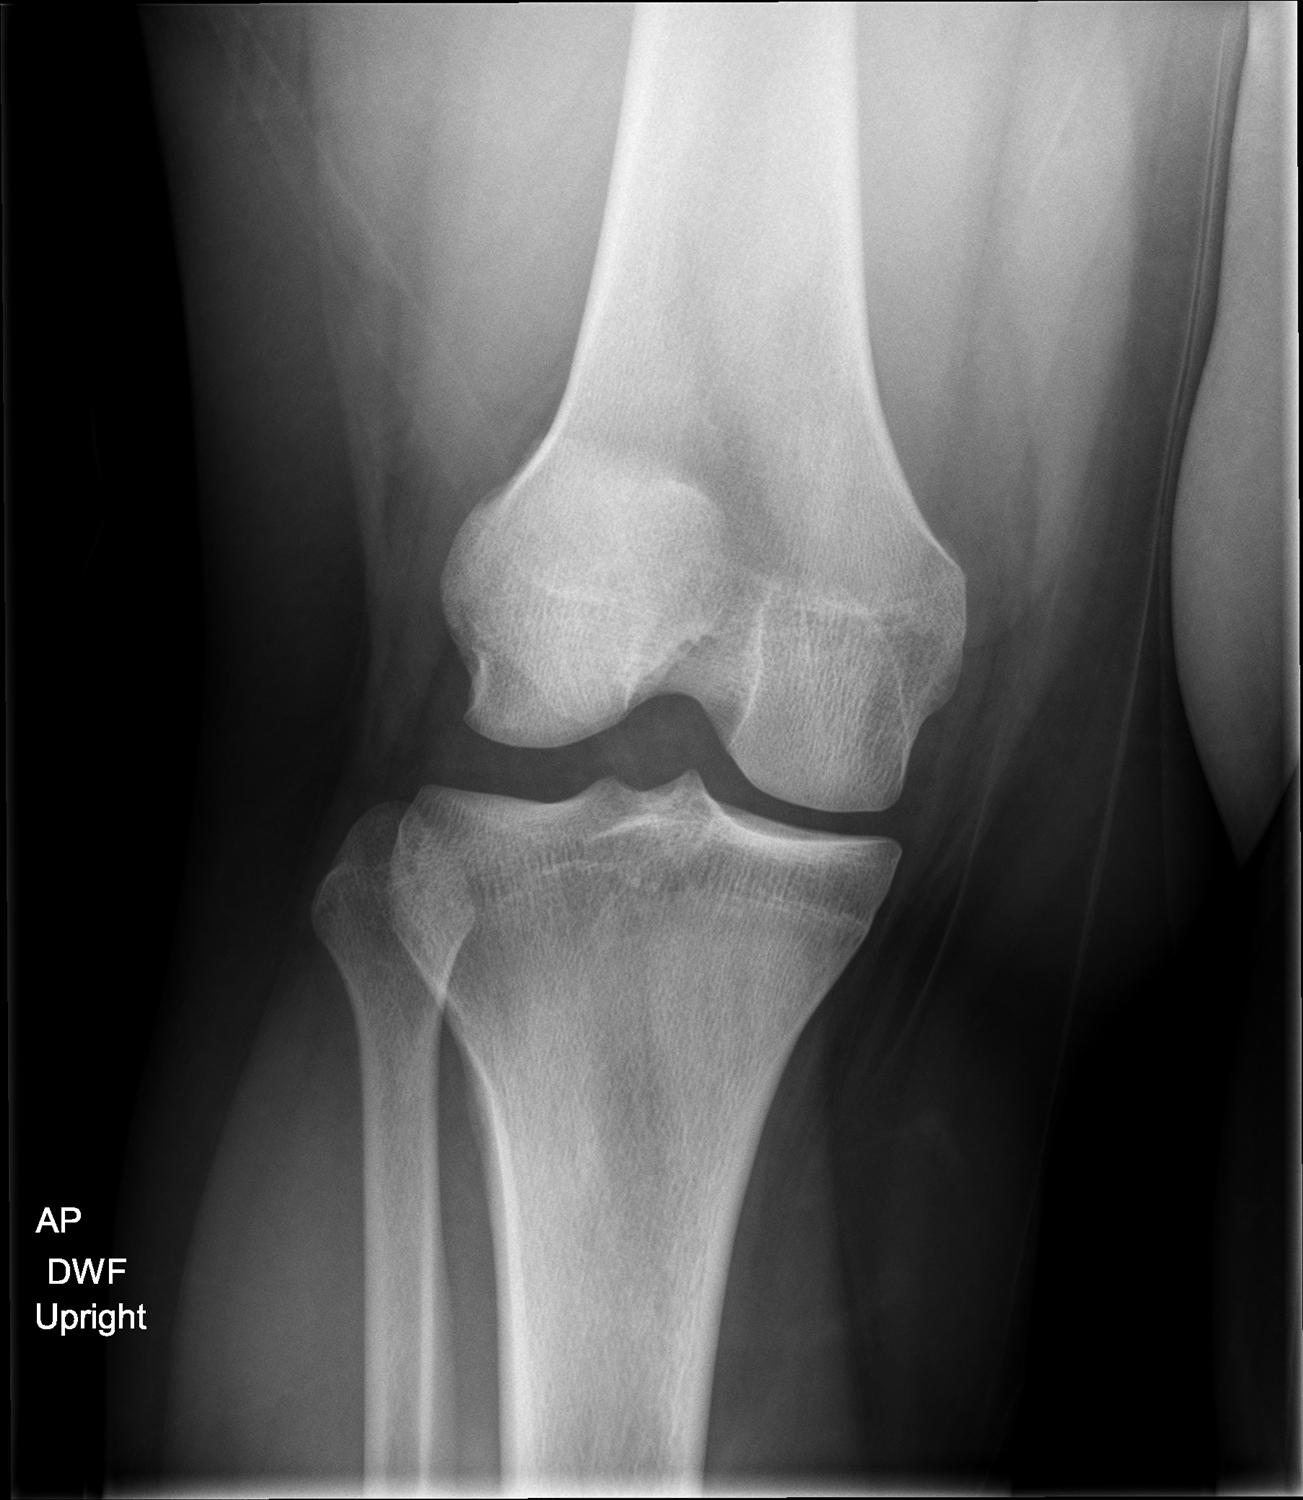

Patient case 1. (a) AP right knee Xray at day 1 showing the avulsion Will Xray Show Lcl Tear It is rare that the. Your lcl (lateral collateral ligament) is a vital band of tissue on the outside of your knee. Athletes are more likely to tear it,. If you have an lcl injury, your doctor will give it a grade: Identify the signs and symptoms suggestive of a lateral collateral ligament injury. Lcl injuries require prompt first aid,. Will Xray Show Lcl Tear.

Plain Xray of the left knee showing lateral collateral ligament Will Xray Show Lcl Tear It is rare that the. Lateral collateral ligament (lcl) injuries of the knee typically occur due to a sudden varus force to the knee and often present in combination with other ipsilateral. If you have an lcl injury, your doctor will give it a grade: Your lcl (lateral collateral ligament) is a vital band of tissue on the outside of. Will Xray Show Lcl Tear.